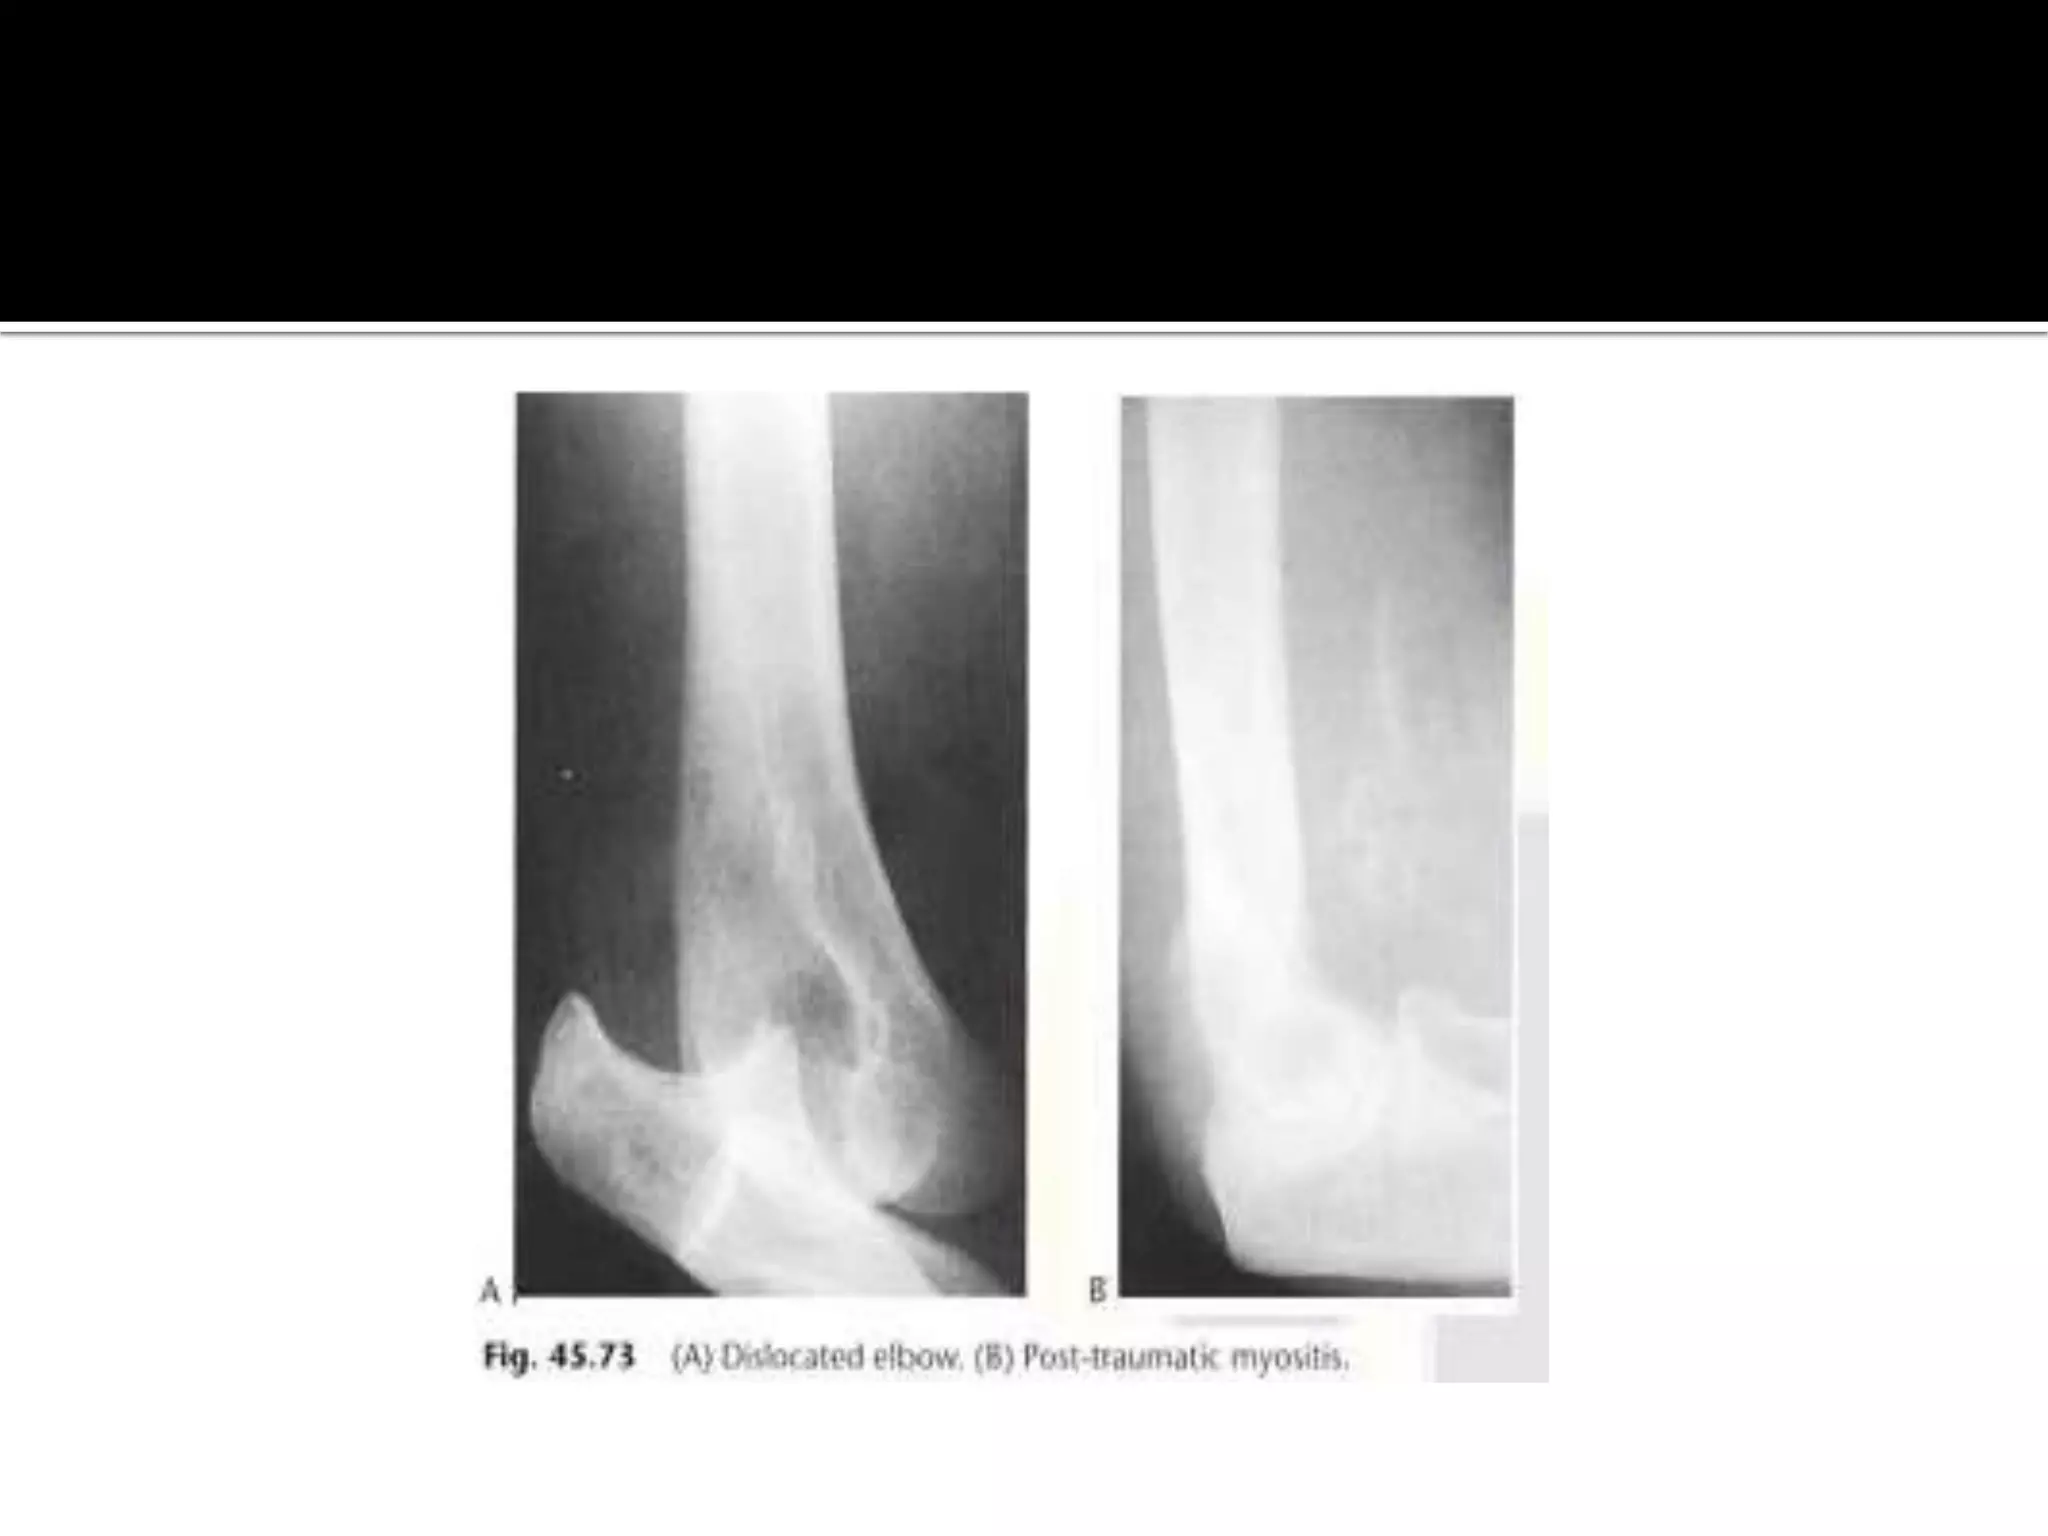

Post-traumatic myositis

 it results in a soft tissue mass which ossifies with a lacy

pattern by 4-8 weeks.

 common sites are the elbow and knee.The ossification

may resolves.

• 45.

Post-traumatic myositis  itresults in a soft tissue mass which ossifies with a lacy pattern by 4-8 weeks.  common sites are the elbow and knee.The ossification may resolves. Paraplegic myocitis ossificans.  it develops in paraplegics within 3-4 weeks below the level of the paralysis.There is hetrotopic periarticular calcification and ossification around the joints particularly the hip with irregular plaques of bone forming.